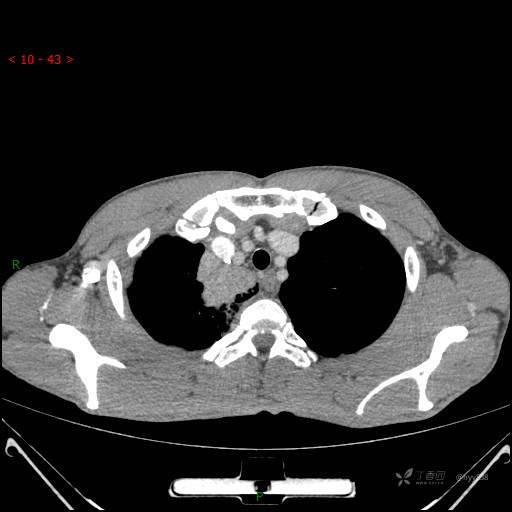

静脉期